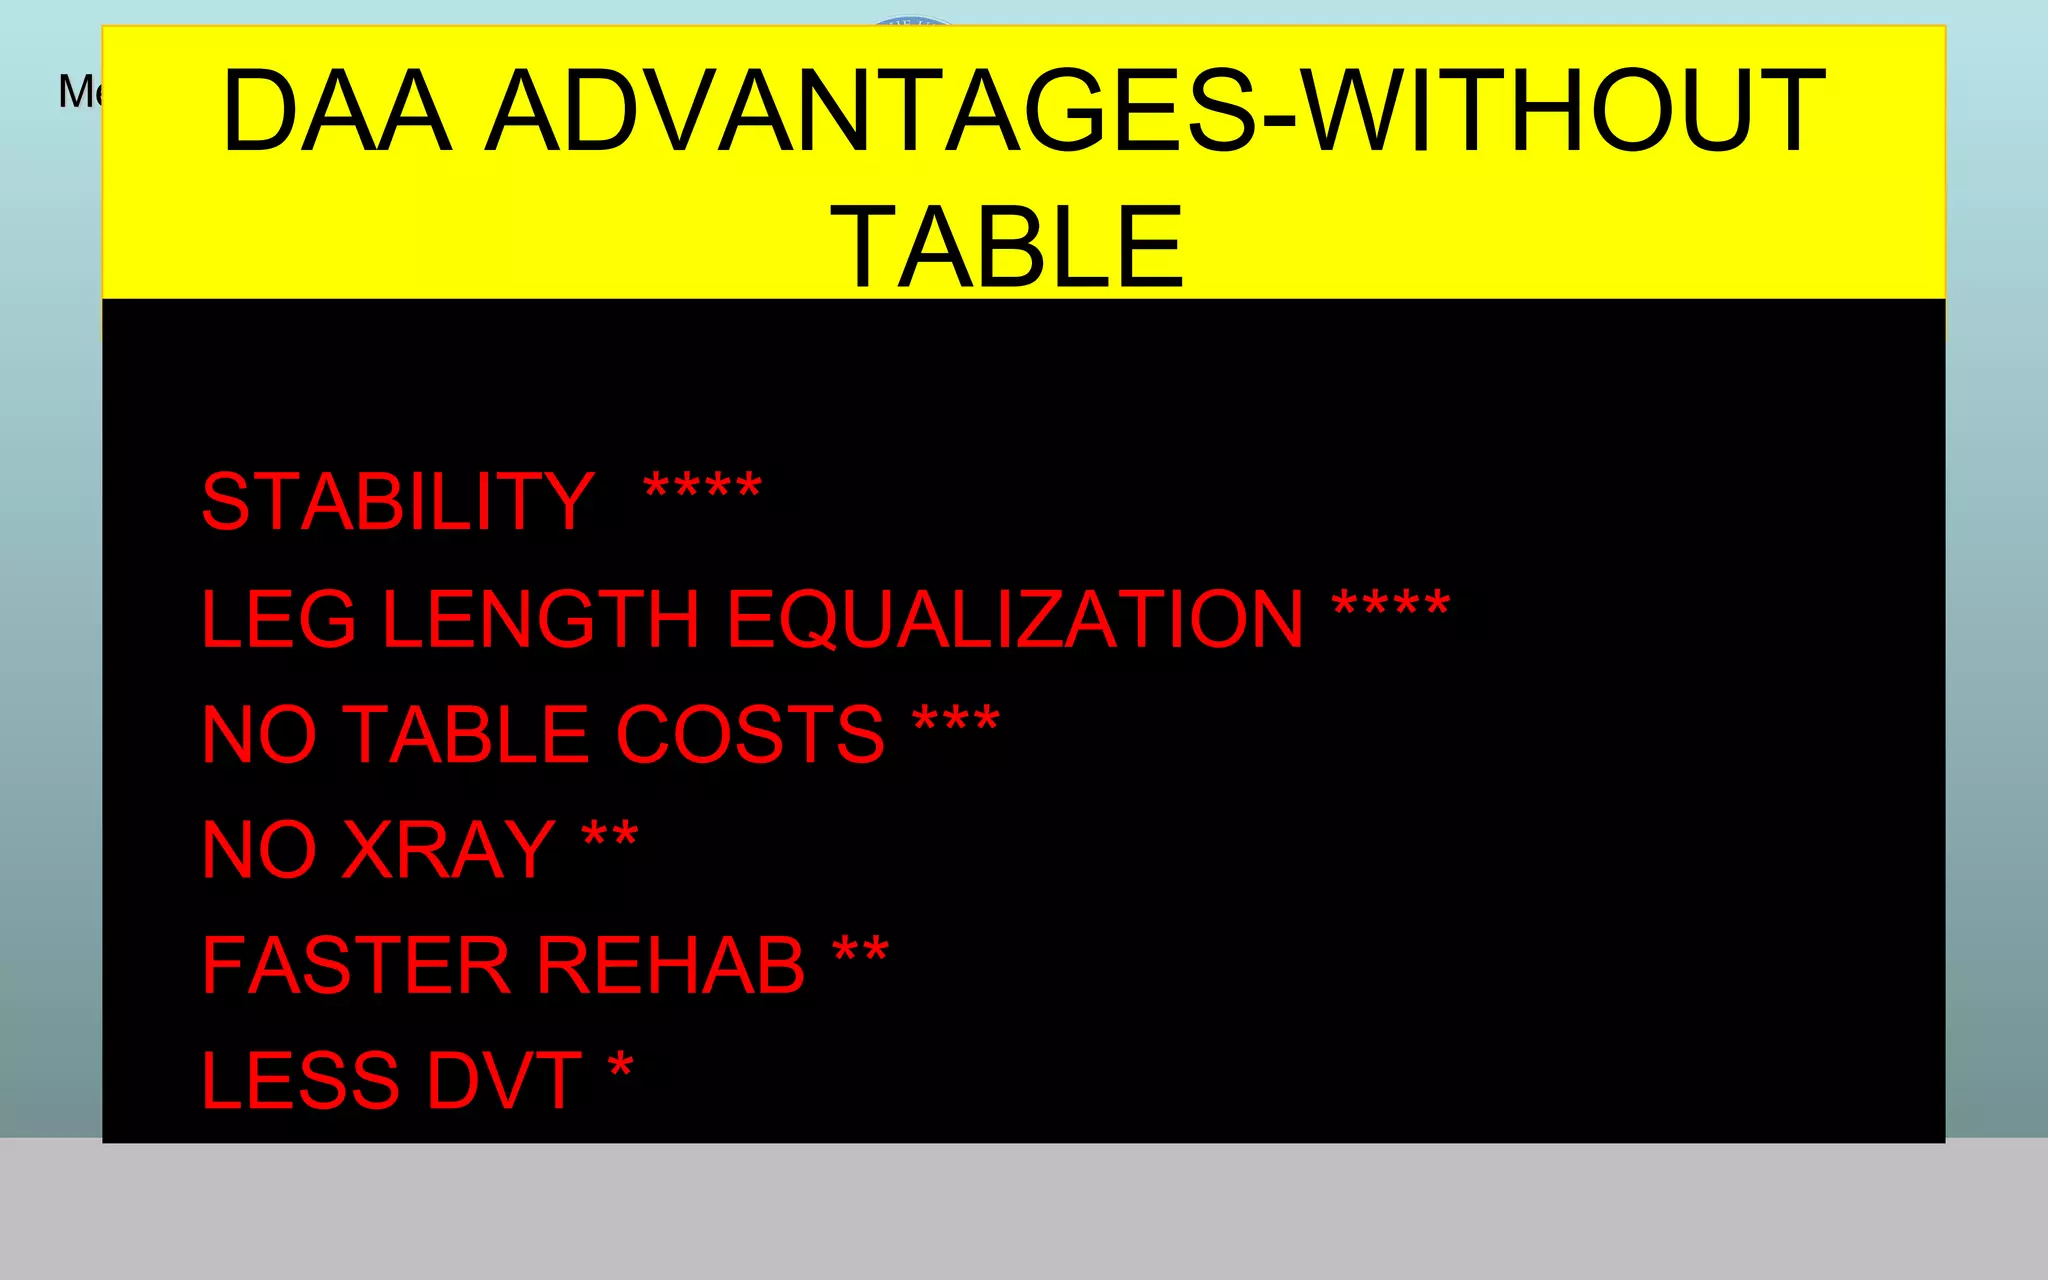

This document discusses the direct anterior approach for total hip arthroplasty. It lists advantages of the direct anterior approach such as increased stability, easier leg length equalization, lower costs by not requiring an operating table, reduced radiation exposure, faster rehabilitation, and lower risk of deep vein thrombosis. The document also discusses the historical background of the direct anterior approach, showing it has been performed since the 1880s. It presents images showing fatty degeneration of muscles and gluteal atrophy after total hip arthroplasty. Finally, it displays graphs comparing outcomes and improvements in quality of life domains between the direct anterior approach and minimally invasive approaches.